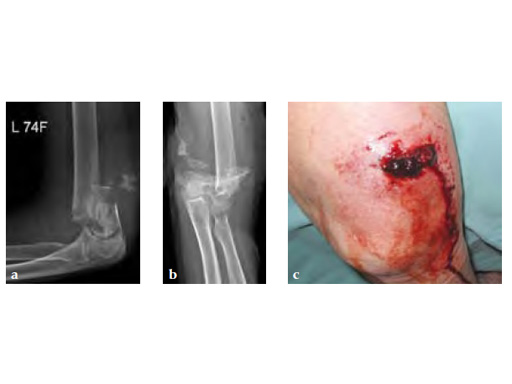

A 75-year-old female pedestrian was hit by a car and sustained a 2 open fracture of the distal humerus and an additional pelvic ring fracture.

Case provided by Martin Hessmann, Fulda, Germany